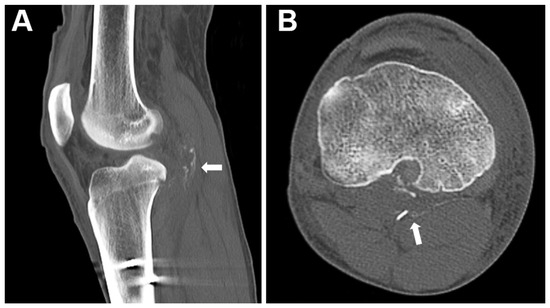

2.2. Surgical Technique

2.4. Evaluation of Tibial Tunnel Position on 3-Dimensional Computed Tomography (3D-CT)

3.2. Tibial Tunnel Position on 3D-CT Scan